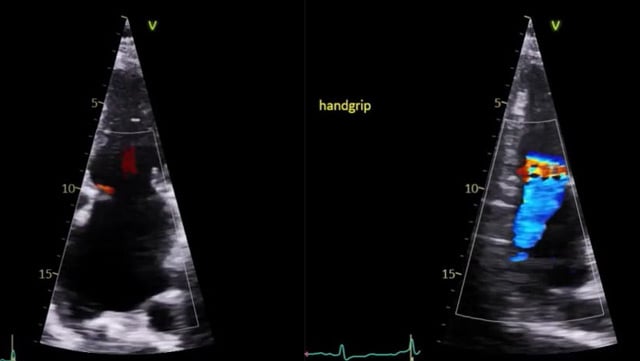

Mitral transcatheter edge-to-edge repair - LIVE Case

29 Sep 2025 – From PCR Gulf Valves 2025

This live educational session from Prince Sultan Cardiac Center in Riyadh offers an in-depth look at mitral transcatheter edge-to-edge repair (TEER) with MitraClip. Learn best practices for patient selection, imaging analysis, operator strategies, and witness a live case procedure to optimize clinical outcomes.

LIVE Educational Case from...